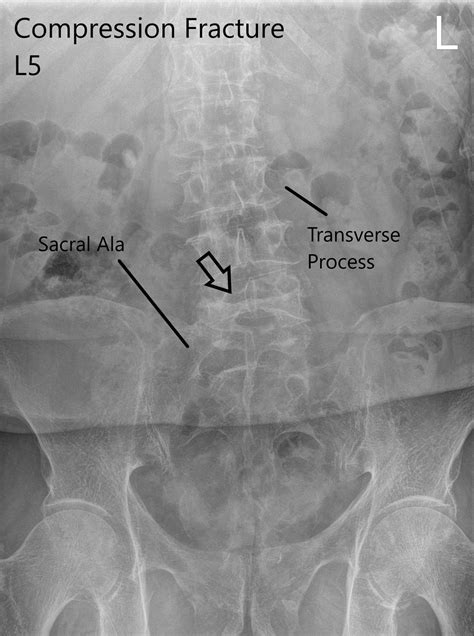

First off, what are we even talking about when we say ‘L1 compression fracture’? L1 refers to the first lumbar vertebra, which is a bone in your lower back. A compression fracture happens when a vertebra collapses, usually due to weakened bone. Think of it like a building where the bricks start to crumble under pressure. This type of fracture is super common, especially in older adults, and is often associated with osteoporosis, a condition that makes bones brittle. However, it can also occur due to trauma, tumors, or other underlying medical conditions. The pain associated with an L1 compression fracture can range from mild to severe, often described as a sharp, stabbing pain that worsens with movement, standing, or sitting. Some people might even experience pain that radiates to other parts of their body. It’s a pretty big deal for someone’s mobility and quality of life, guys, so getting the diagnosis and coding right is absolutely paramount. We need to be precise because it directly impacts treatment plans, insurance claims, and statistical tracking of these injuries.